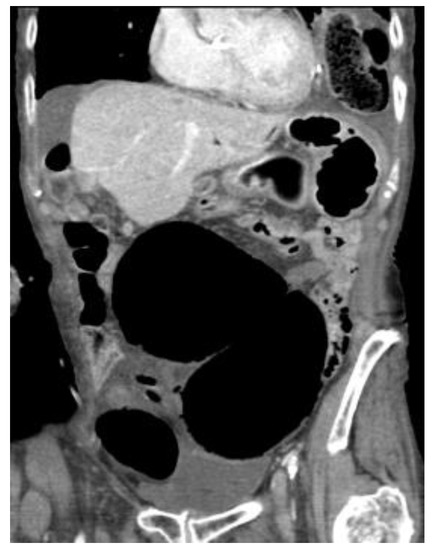

4.4.2. Computerised Tomography (CT) Scan

| Abdominal radiograph | 11 (68.75%) | Five patients had CT as the only imaging. |

| Non-specific bowel loops/SBO | 5 (46%) | |

| Classical single loop of large bowel | 6 (54%) | |

| CT Abdomen and pelvis | 15 | One patient operated without CT. |

| CV not described | 1 | |

| CV correctly identified | 14 (93.3%) | |

| Caecal diameter >10 cm | 10 (67%) | |

| Whirl sign | 12 (80%) | |

| Split-wall sign | 13 (86.6%) | |

| X-marks-the-spot sign | 14 (93.3%) | |

| Double transition point | 13 (86.6%) | |

| Ileocaecal twist | 13 (86.6%) | |

| Central appendix | 11 (73.3%) |